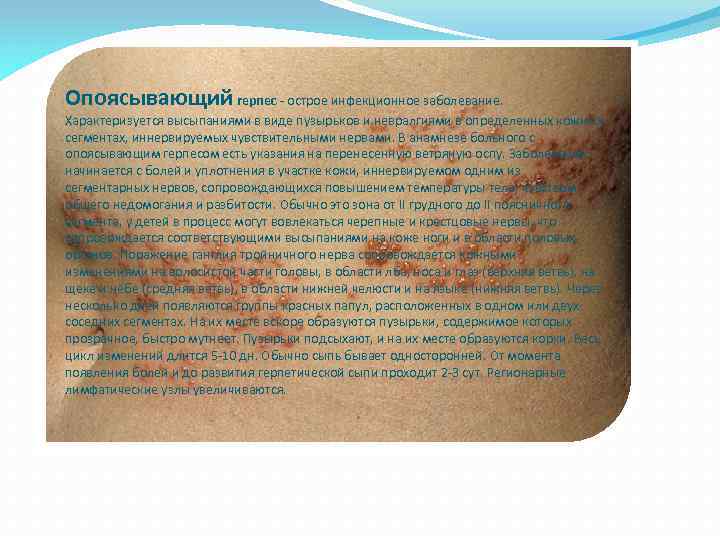

Медицинские снимки и изображения опоясывающего герпес вируса

Раздел: Фотодневник открытий